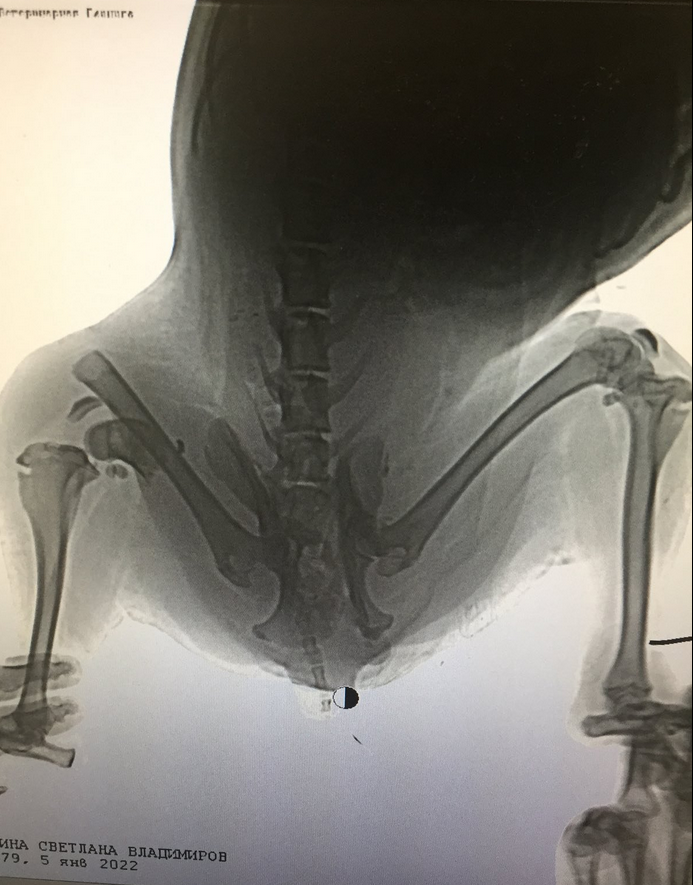

Было принято решение доставить животное в клинику ОГБУ «Симбирский референтный центр ветеринарии и безопасности продовольствия», чтобы сделать комплексное обследование и рентгеновский снимок.

- Собаке была оказана вся необходимая ветеринарная помощь, были взяты анализы крови. Рентгеновский снимок показал, что у неё перелом бедренной кости и таза. В настоящее время назначено лечение. Также сотрудниками государственной ветслужбы устанавливаются причины получения собакой травм, - сообщает пресс-служба Агентства ветеринарии.